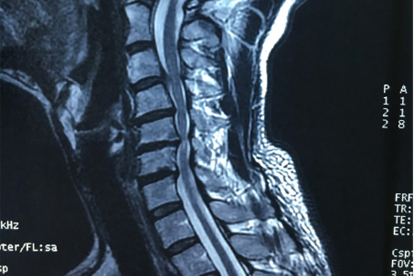

针对交感型颈椎病和小关节紊乱,推拿医师运用旋转扳法等手法可纠正颈椎小关节微错位,减轻对周围神经血管的刺激。需通过X光或MRI明确关节位置后再行手法复位,盲目操作可能造成脊髓损伤等风险。